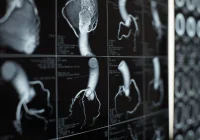

Three different VR technologies have been found to be commonly used in healthcare education and practice. These technologies offer immersive virtual environments that provide a favourable learning experience for both medical practitioners and students.

Three Leading Healthcare VR Technologies

An integrative review, carried out by researchers from Finland (Mäkinen et al. 2020), has identified these three VR technologies generally used as learning tools in healthcare.

Haptic device simulators. These devices are the most widely used in training as they offer more immersive learning experiences and improved realism. Haptics enable the user to feel a natural or synthetic mechanical environment by touch; this is achieved by applying forces, vibrations, or motions to the user. Through such simulations, the user is able to develop fine motor skills that are important in performing surgical procedures, for example.

Computer-based simulations. This kind of technology is effective especially in nursing education, as it provides real-time visualisation and enables the user to interact with the virtual environment, then receiving computer-generated feedback for their actions. Using these kind of simulations helps the learner combine theoretical knowledge with practice.

Head-mounted displays (HMDs). These systems offer the most immersive learning experience, engaging the learner in a 3D world using a head-mounted display. Total immersion is made possible through the use of haptic, auditory and other non-visual technologies. Of the three healthcare VR technologies, HMD is the least used possibly because this kind of technology is relatively new in the field of healthcare.